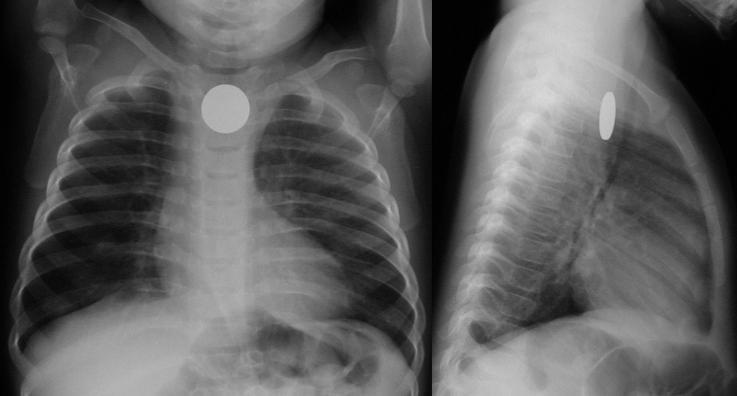

Signe très important : les piles boutons ont un double contour (sur les radios de face) et une petite marche d’escalier sur le contour (sur les radios de profil)

Il n’y a pas de double contour sur une pièce de monnaie

La grande crainte lors d’un corps étranger œsophagien est la pile bouton, qui peut faire des dégâts irréparables en quelques minutes sur la muqueuse œsophagienne par contact. Elle peut être différenciée à la radio d’une pièce de monnaie (corps étranger beaucoup plus fréquent), grâce au double contour que l’on aperçoit facilement sur les radios de face et de profil. Une pièce de monnaie présente un contour lisse. Insérer image « Figure3.jpg ».